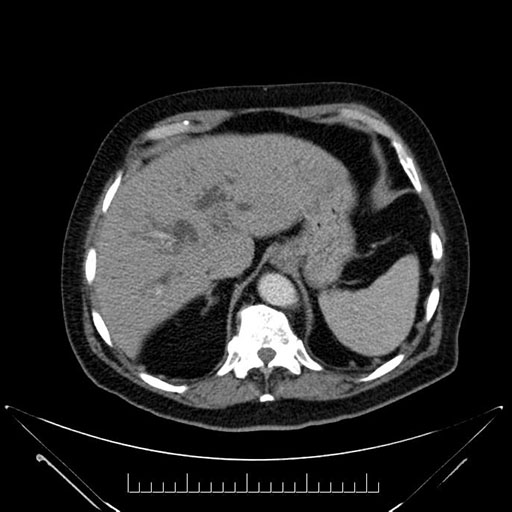

Whipple (pancreaticoduodenectomy) [case 7]

Imaging Analysis

Look through the patient's CT scan to identify any areas of concern for the necessary procedure.

Axial - stented

Based on your CT findings, which issue(s) would give reason for "planned slowing down moment(s)" in this case?

Considering a standard Whipple procedure, what step(s) of the operation would you do differently in this case?